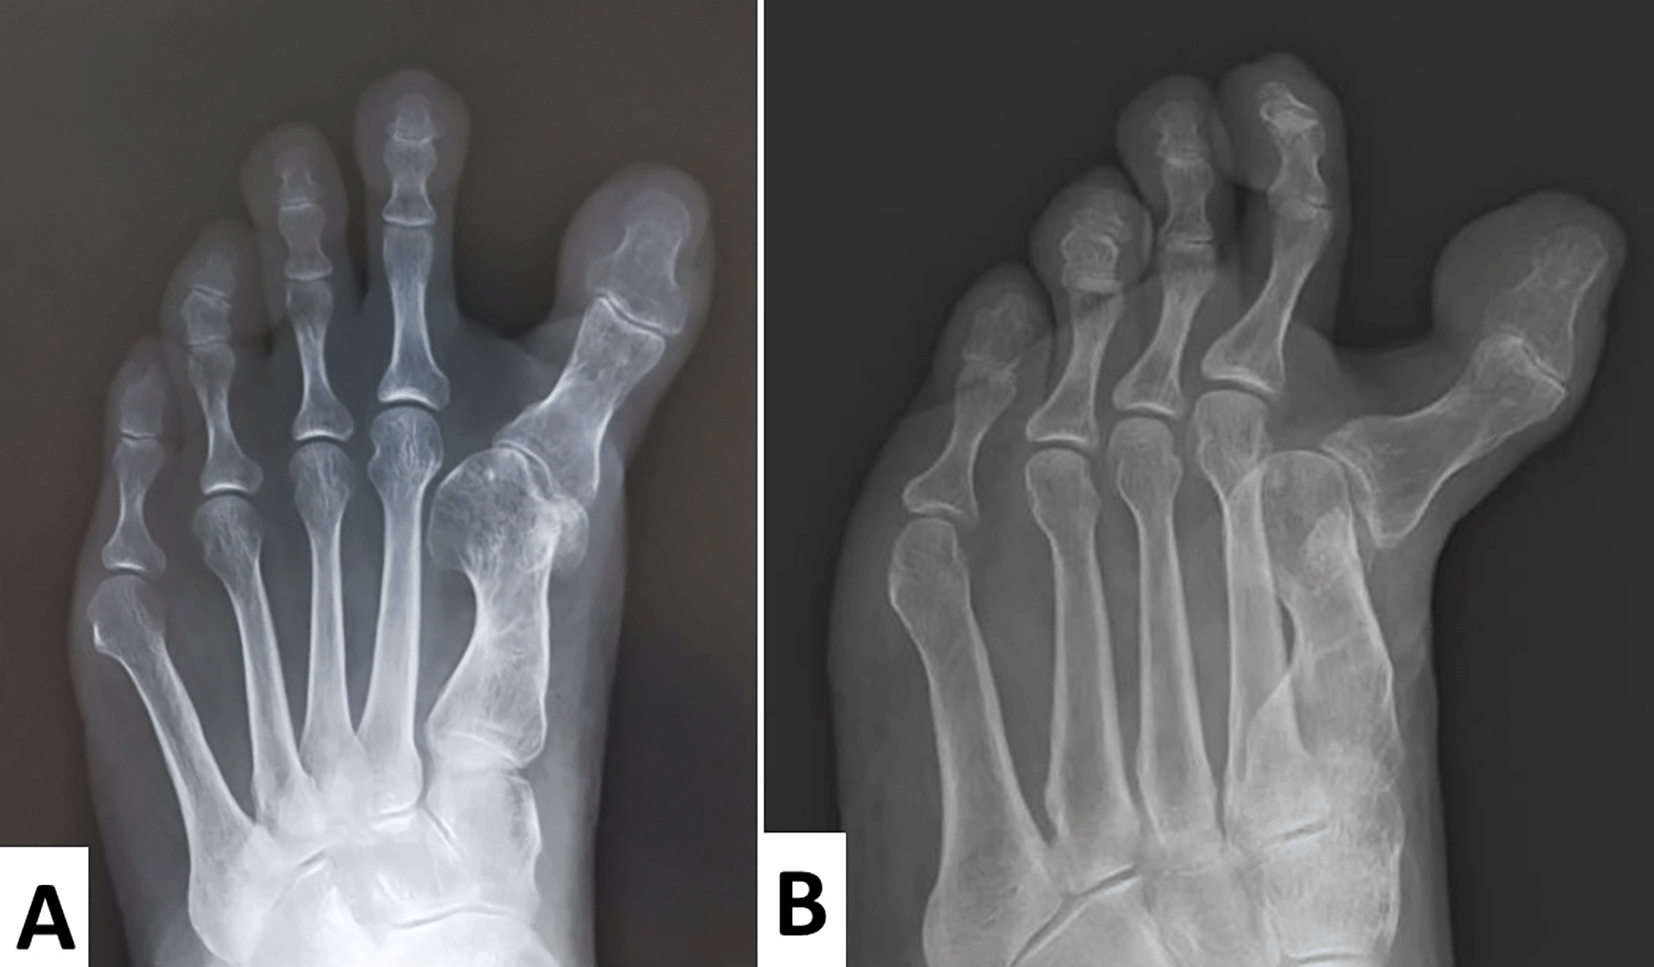

Radiographs showed that the hallux valgus angle (HVA) was -28° (Figure 3A). The intermetatarsal angle between the first and the second metatarsus (M1M2A) was 0° (normal range, 6°–9°), which meant that the first and second metatarsal bones were parallel (Figure 3A). As the tibial sesamoid shifted medially, and the fibular sesamoid was absent, excessive medial eminence resection might have been performed. An oblique view of the foot demonstrated that the proximal phalanx subluxated dorsally (Figure 3B).

Radiographs show that the hallux valgus angle was -28°.

The intermetatarsal angle, which should be approximately 6°–9°, is 0°. This indicates that the first and second metatarsal bones are parallel.

The tibial sesamoid has shifted medially and the fibular sesamoid is absent. Excessive medial eminence resection might have been performed.